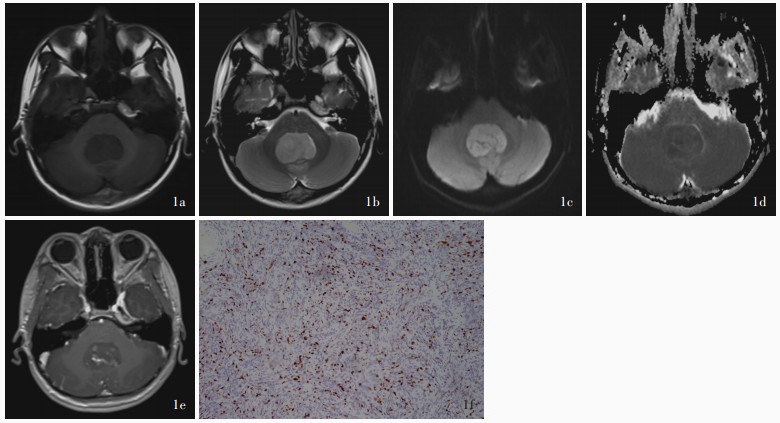

目的: 探讨儿童后颅窝常见肿瘤的影像学诊断与鉴别诊断方法,并按照先定位诊断再定性诊断的思路,基于DWI是否弥散受限提出儿童后颅窝常见肿瘤的诊断流程图。方法: 共纳入2021年1月至2024年1月在复旦大学附属华山医院予以手术切除的118例儿童后颅窝肿瘤患者,均行头部CT和MRI检查,并据此进行术前定位和定性诊断,分别以术中所见和术后病理学检查为诊断“金标准”,判断术前定位诊断和定性诊断的准确性;再基于DWI是否弥散受限提出儿童后颅窝常见肿瘤的诊断流程图。结果: 共118例后颅窝肿瘤患儿定位和定性诊断为第四脑室肿瘤计41例,包括髓母细胞瘤27例、毛细胞型星形细胞瘤7例、室管膜瘤5例、脉络丛乳头状瘤1例、形成菊形团的胶质神经元肿瘤1例;脑干肿瘤38例,包括弥漫性中线胶质瘤,H3 K27变异型24例、毛细胞型星形细胞瘤5例、海绵状血管瘤3例、儿童型弥漫性高级别胶质瘤(倾向弥漫性中线胶质瘤,H3野生型)2例、节细胞胶质瘤2例、非典型性畸胎样/横纹肌样肿瘤1例、儿童型弥漫性低级别胶质瘤1例;脑桥小脑角肿瘤计9例,包括毛细胞型星形细胞瘤3例、胆脂瘤2例、髓母细胞瘤1例、弥漫性中线胶质瘤,H3 K27变异型1例、毛细胞黏液型星形细胞瘤1例、尤文肉瘤1例;小脑肿瘤计30例,包括毛细胞型星形细胞瘤15例、髓母细胞瘤7例、海绵状血管瘤2例、室管膜瘤1例、儿童型弥漫性低级别胶质瘤1例、儿童型弥漫性高级别胶质瘤(倾向弥漫性中线胶质瘤,H3野生型)1例、胚胎发育不良性神经上皮肿瘤1例、错构瘤1例和肾外横纹肌样瘤小脑转移瘤1例。定位诊断,术前CT的定位诊断准确率为93.22%(110/118),MRI的定位诊断准确率达100%(118/118)。定性诊断,74例(62.71%)患儿定性诊断准确,23例(19.49%)诊断笼统,21例(17.80%)诊断错误。儿童后颅窝肿瘤的影像学鉴别诊断集中于髓母细胞瘤、毛细胞型星形细胞瘤、室管膜瘤、弥漫性中线胶质瘤,H3 K27变异型。位于脑干外的髓母细胞瘤、毛细胞型星形细胞瘤和室管膜瘤的DWI弥散受限发生率分别为100%(35/35)、4%(1/25)和5/6,3种肿瘤之间差异有统计学意义(Z=-5.601,P=0.000);位于脑干的弥漫性中线胶质瘤,H3 K27变异型和毛细胞型星形细胞瘤的DWI弥散受限发生率为79.17%(19/24)和1/5,两种肿瘤之间差异亦有统计学意义(Fisher确切概率法:P=0.038)。结论: 儿童后颅窝肿瘤早期诊断较为困难,DWI是鉴别诊断的重要依据,基于DWI是否弥散受限提出的儿童后颅窝常见肿瘤诊断流程图有望提高术前诊断的准确性。

Objective: To investigate the imaging diagnosis and differential diagnosis methods for common tumors in the posterior fossa of children, and to propose a flow chart for the diagnosis of common tumors in the posterior fossa of children based on the limited diffusion of DWI according to the idea of localization diagnosis followed by qualitative diagnosis. Methods: A total of 118 pediatric patients with posterior fossa tumors who underwent surgical resection in Huashan Hospital, Fudan University from January 2021 to January 2024 were enrolled, and all of them underwent head CT and MRI examinations, and preoperative localization diagnosis and qualitative diagnosis were carried out accordingly. Then, based on whether DWI was diffusion limited, a flow chart for the diagnosis of common tumors in the posterior fossa of children was proposed. Results: A total of 118 children with posterior fossa tumors were localization and qualitatively diagnosed, including 41 cases of fourth ventricular tumors, including medulloblastoma (27 cases), pilocytic astrocytoma (7 cases), ependymoma (5 cases), choroid plexus papilloma (one case), and rosette-forming glioneuronal tumor (RGNT, one case). There were 38 cases of brainstem tumors, including 24 cases of diffuse midline glioma, H3 K27-altered, 5 cases of pilocytic astrocytoma, 3 cases of cavernous hemangioma, 2 cases of pediatric-type diffuse high-grade glioma (prone to diffuse midline glioma, H3 wild type), 2 cases of ganglio glioma, one case of atypical teratoid/rhabdoid tumor (AT/RT), and one case of pediatric-type diffuse low-grade glioma. There were 9 cases of cerebellopontine angle (CPA) tumors, including 3 cases of pilocytic astrocytoma, 2 cases of cholesteatoma, one case of medulloblastoma, one case of diffuse midline glioma, H3 K27-altered, one case of pilomyxoid astrocytoma, and one case of Ewing sarcoma. There were 30 cases of cerebellar tumors, including 15 cases of pilocytic astrocytoma, 7 cases of medulloblastoma, 2 cases of cavernous hemangioma, one case of ependymoma, one case of pediatric-type diffuse low- grade glioma, one case of pediatric-type diffuse high- grade glioma (prone to diffuse midline glioma, H3 wild type), one case of dysembryoplastic neuroepithelial tumor (DNT), one case of hamartoma, and one case of extrarenal rhabdomyomatoid tumor cerebellar metastases. Localization diagnosis, the accuracy of preoperative CT was 93.22% (110/118), while the accuracy of preoperative MRI was 100% (118/118). Qualitative diagnosis, 74 cases (62.71%) had accurate qualitative diagnosis, 23 cases (19.49%) had general diagnosis, and 21 cases (17.80%) had wrong diagnosis. The imaging differential diagnosis of posterior fossa tumors in children focuses on medulloblastoma, pilocytic astrocytoma, ependymoma, and diffuse midline glioma, H3 K27-altered. The incidence of limited diffusion of DWI in medulloblastoma, pilocytic astrocytoma and ependymoma outside the brainstem was 100% (35/35), 4% (1/25) and 5/6, and the difference among the three tumors was statistically significant (Z =-5.601, P = 0.000). The incidence of limited diffusion of DWI in diffuse midline glioma, H3 K27-altered and pilocytic astrocytoma in the brainstem was 79.17% (19/24) and 1/5, and the difference between the two tumors was also statistically significant (Fisher's exact possibility: P = 0.038). Conclusions: The early diagnosis of posterior fossa tumors in children is difficult, and DWI is an important basis for differential diagnosis.